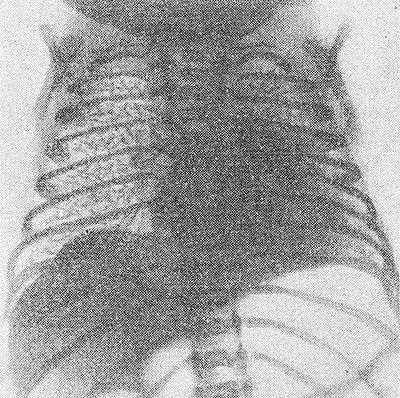

Рис. 2. Рентгенограмма грудной клетки ребенка 15 часов жизни, страдающего гиалиново-мембранной болезнью: на всем протяжении правого легкого видна характерная сетчатость легочного рисунка, ателектазы в левом легком.

Основной методикой исследования является рентгенография грудной клетки. Рентгенологическими признаками Г.-м, б. н. на рентгенограмме легких (рис. 2) являются: 1) характерная патологическая сетчатость легочного рисунка; иногда наблюдаются беспорядочно расположенные участки уплотнения легочной ткани (ателектазы), чередующиеся с участками просветления за счет локального вздутия легких; 2) наличие светлых полосок бронхиальных разветвлений, различимых на фоне малопрозрачного легкого; 3) в тяжелых случаях имеется диффузное понижение прозрачности легочных полей (так наз. белое легкое). Отмечается необычная форма грудной клетки — с опущенными ребрами. Иногда на рентгенограмме могут наблюдаться пневмоторакс (см.), интерстициальная и медиастинальная эмфизема (см.), возникающие в связи с разрывом бронхиол.